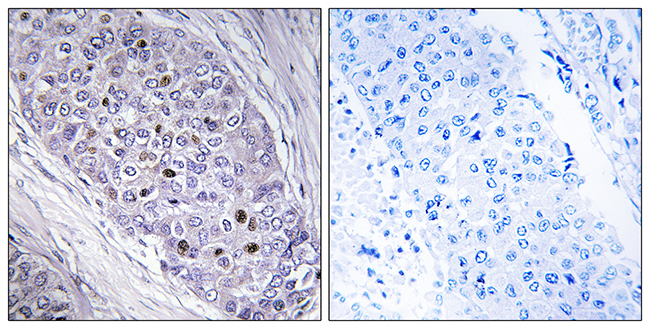

Anti-LDOC1 AntibodyA98864

ApplicationsELISA, ImmunoHistoChemistry

ReactivityHuman, Mouse

- SizePrice